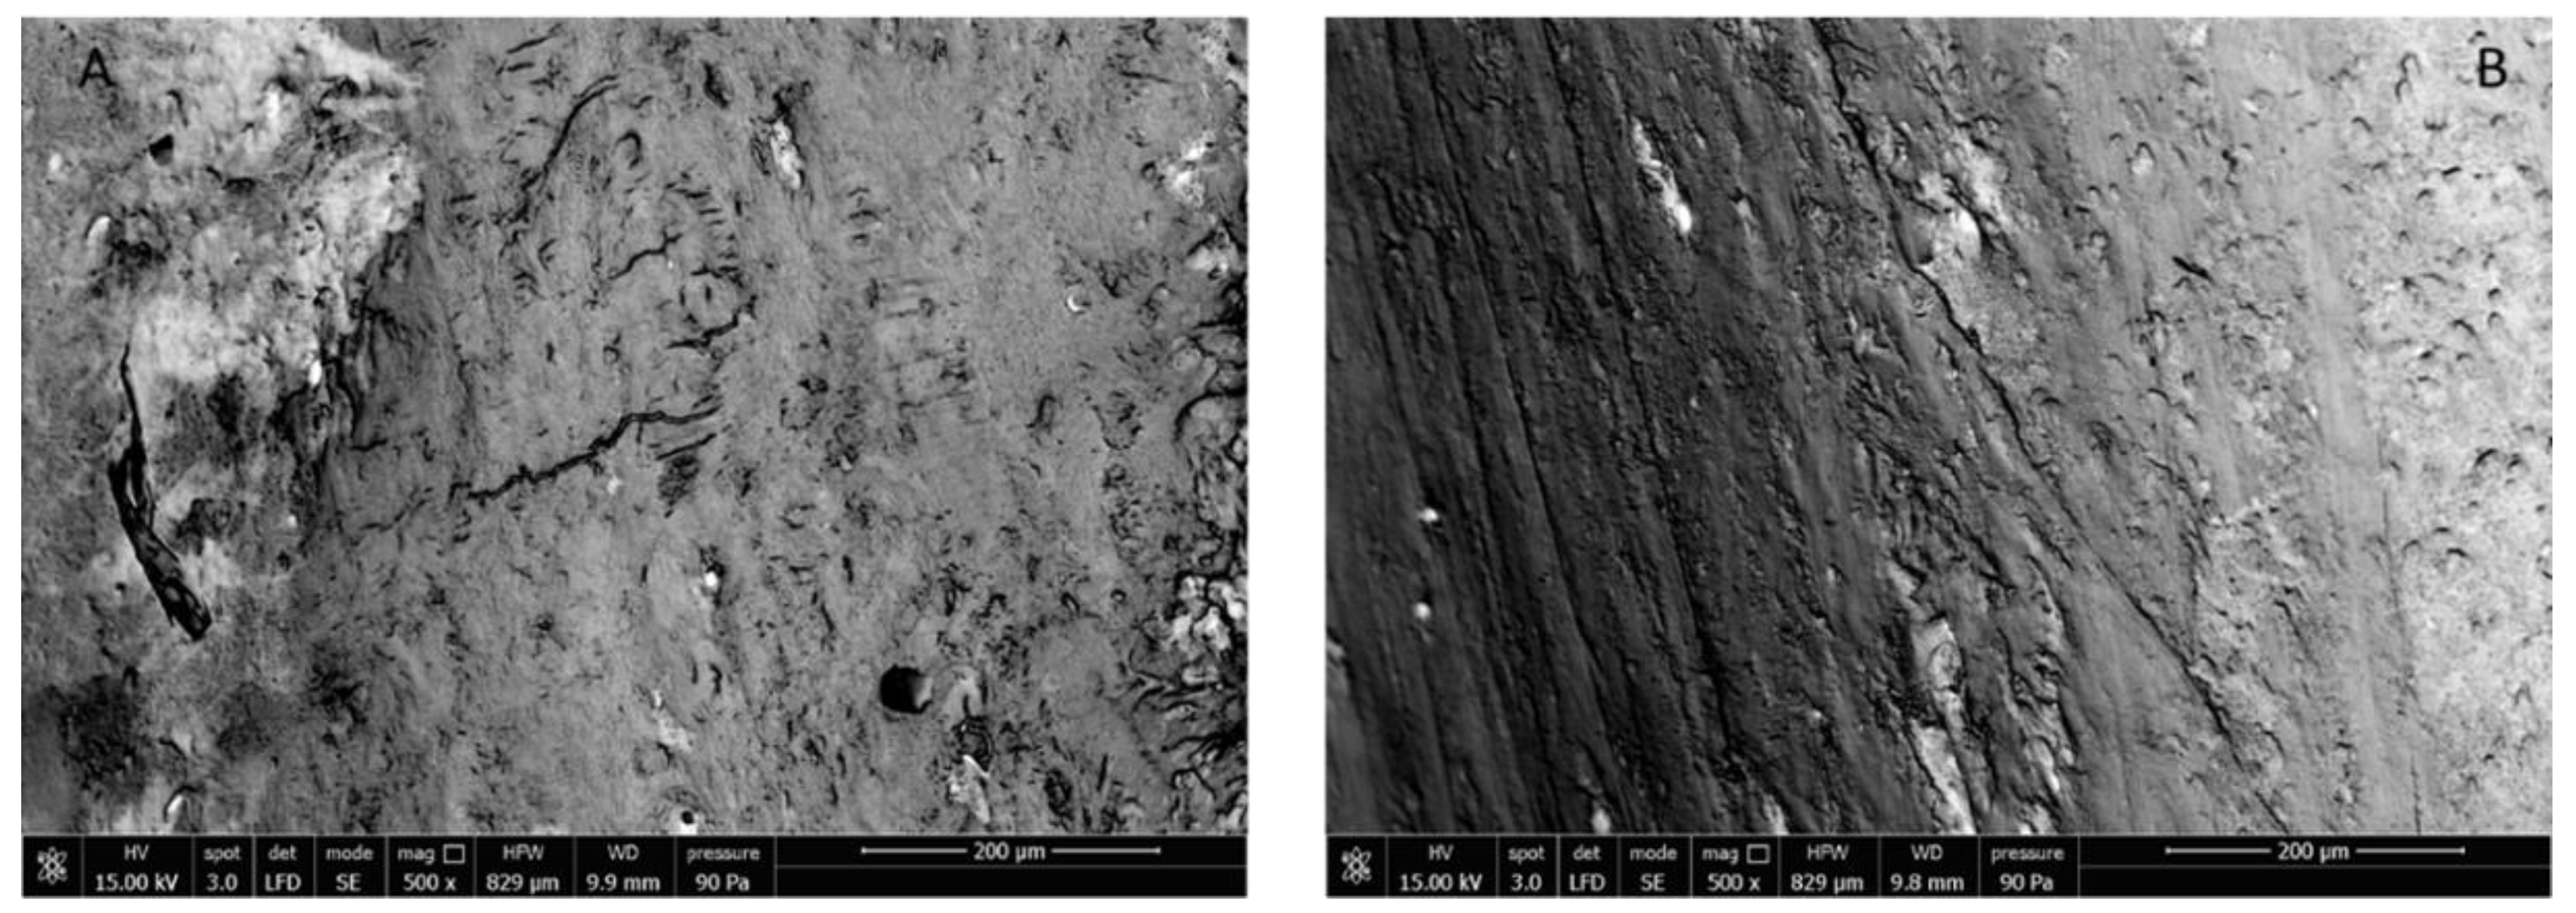

3.3.3. Rat Femur Morphological Characterization